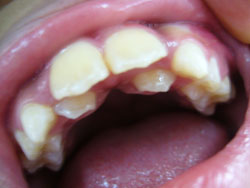

*Hô răng hàm trên, hô hàm trên:

- Hô răng hàm trên và hô hàm trên là một lệch lạc khá phổ biến, làm cho khuôn mặt không thẩm mỹ.

Hô răng hàm trên là tình trạng răng cửa hàm trên trên nghiêng nhiều ra trước, trong khi xương hàm trên vẫn bình thường theo tương quan chiều trước sau.

Hô Hàm trên là tình trạng hàm trên nhô quá về phía trước, hoặc hàm dưới lùi quá về phía sau